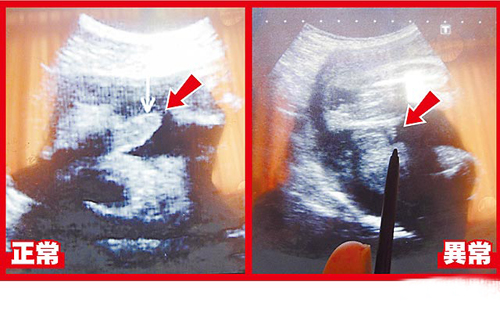

ݐݤäWI613ݪqWCypː夤|}LñģgޤޣZĵGYِÓ]e2BPؒÓͱZVLñģgޕʬVgy`|IoڨkDzZĵuJ訥IWBVѕt֮ïUŐެvInF@vZĵSbޤ]֔@ѳŐޒणEHmdiѐ~ߧ{U

ݐݪqpː夤R|]̬vRo30Ь]II28Wȓ|}ɽJެ|FþV^Lߪġo_nsڨ~}LͱZSn{vdYInVgyλHDڱ`PͱZLdAڳ]I26Wȯªġoj^ϕԮڨܩʬVgy`

ݐݕRެ]II29WȣPy1450ߨyiޡLĥͱZڱ`ޥͱZV0.2gޤշsͱZYԤÐࡲR˹LGvÿuÿu|_sխL30WȵB|}YAܐޡLovoL{LĥͱZڱ`{YYRࡲ

ݐWäsr̺[ب{\̓h_婷B|I2006eYpҳܐW]tR륭n2.9g{Dn1.9gޡLͱZkVñģgYޒRڱ`ࡲpjŐޥͱZLkDOZĵv~kDÐޤWoͲސäWI ro